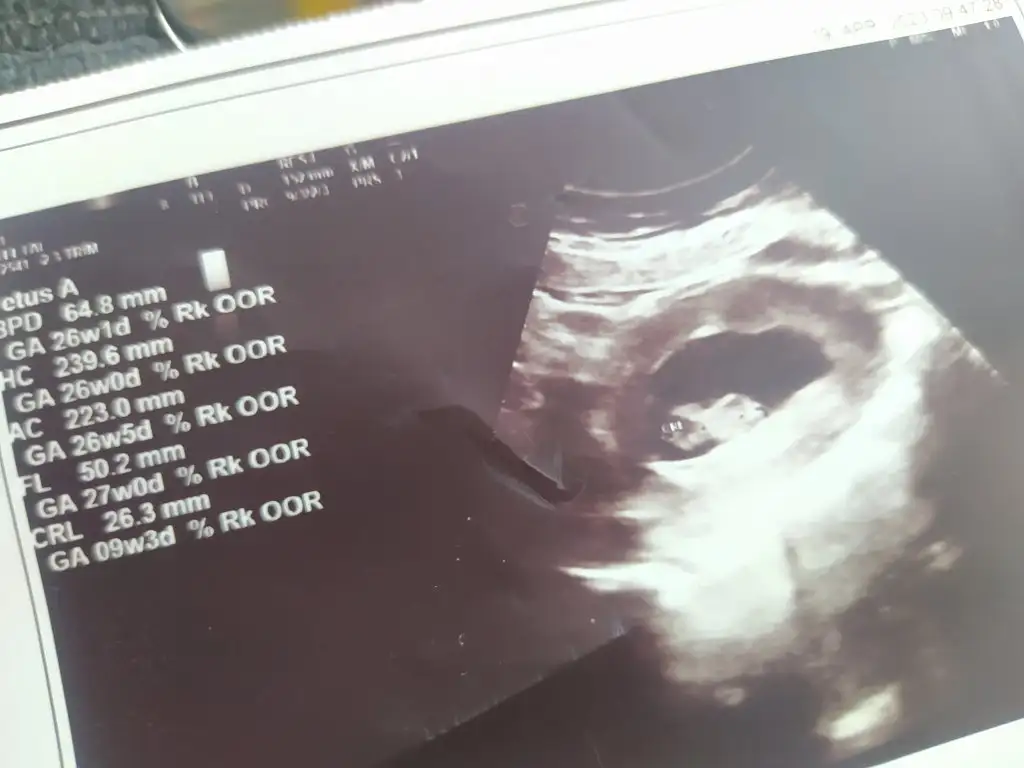

Karından görebildik çok şükür bebekler aynı duruyo hemen hemen ama birinin kesesi küçük kendi doktorum bişey demedi buda riski var tabi dedi ikiz gebelik riskinden bahsetti buraya gelme doğumda dedi burası ikizi kaldıramaz araştırma hastanesine falan gidersin dedi gittiğim hastaneyi söyledim hem oraya hem buraya gel sıkı takipte ol kanlarını burda verirsin dedi 5 tüp kan 2 idrar verdim